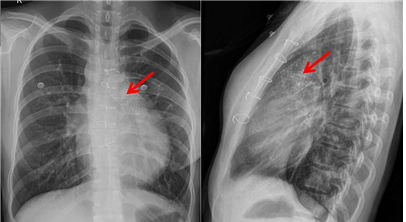

연구팀은 이 판막을 2011년부터 동물에 이식해왔으며, 식품의약품안전처의 허가(2015년 7월)를 받아 2016년 2월 첫 임상시험에 돌입했다. 그리고 10년이 넘는 긴 여정 끝에 그해 10월 10번째 환자에게 성공적으로 판막을 이식하고, 최근 6개월간의 추적관찰을 마쳤다.

이번에 임상시험에 참가한 판막질환 환자 10명은 6개월의 추적관찰 기간 동안 심각했던 역류가 최소화됐으며, 면역거부반응도 나타나지 않았다. 역류가 거의 사라지면서, 우심실의 부피도 평균 32.1%나 줄었다.

또 가슴을 여는 수술 대신 스텐트 시술로 판막을 이식해, 중환자실을 거치지 않고 일반병실에서 4일 내에 퇴원했으며, 이식으로 인한 특별한 합병증도 나타나지 않았다.